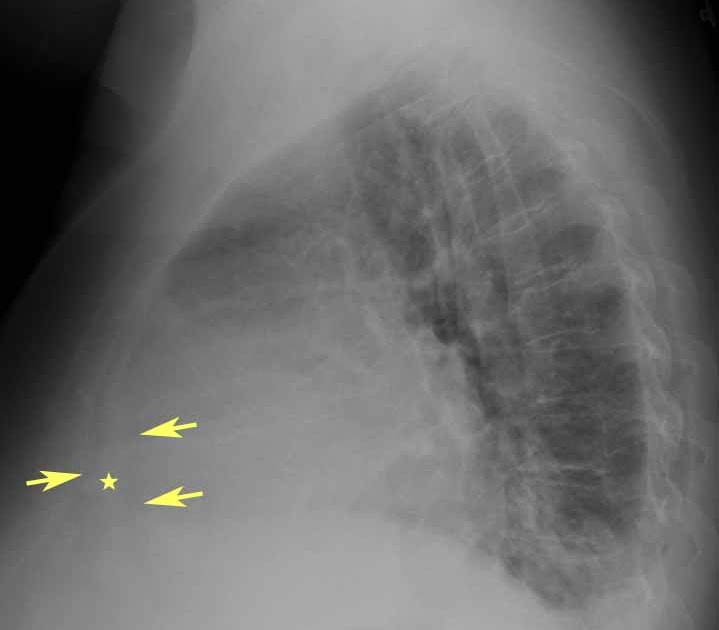

RiT radiology Pericardial Effusion on Lateral Chest Radiograph Chest X Ray Findings In Pericardial Effusion This was due to pericardial effusion and is a good example of. Ct confirms the presence of a pericardial effusion as well as numerous axillary. Left pleural effusion is common with pericardial effusion, while bilateral pleural effusion is seen more often with congestive heart failure. Chest X Ray Findings In Pericardial Effusion.